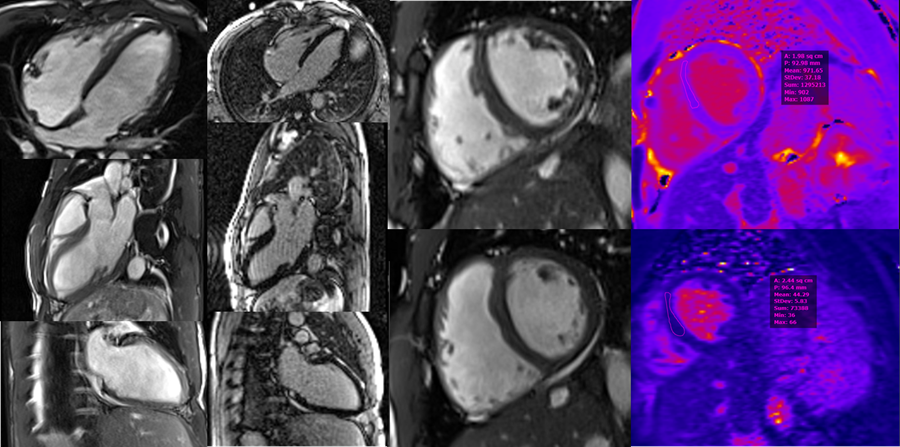

For this patient, an ST-segment elevation myocardial infarction code was canceled after a point-of-care echocardiogram had findings of no segmental WMAs. A diagnostic left heart catheterization demonstrated normal coronary arteries without anomalous origin. He was monitored in the cardiac intensive care unit for further evaluation of syncope. Neither ventricular arrythmia (VA) nor atrioventricular block was seen on 5 days of telemetry monitoring. As his laboratory study values improved, cMRI performed 36 hours later had findings of normal LV size and function, upper limit of normal RV size and function (RV ejection fraction 57%) with no scar on late gadolinium enhancement, and normal T1 (972 msec) and T2 (44 msec) mapping times consistent with athlete's heart (Image 2). TWI resolved in leads V3 and V4, although they persisted in leads V1 and V2 (Image 3). A maximal intensity exercise stress test had unremarkable findings, including no evidence of VA. His syncope was attributed to extreme volume depletion and ECG changes from baseline abnormalities exaggerated by rhabdomyolysis. He was discharged with recommendations for adequate hydration and further remote rhythm monitoring. After no abnormalities were found on remote rhythm monitoring and shared decision-making, he returned to exercise without restrictions.

Image 2

CMR images demonstrating normal LV size (LVEDVi 94 mL/m2) and function (LVEF 53%). ULN RV size (RVEDVi 111 mL/m2) and normal RV systolic function (RVEF 57%). Normal T1 (972 msec) and T2 (44 msec) mapping times. No evidence of scar on LGE imaging. Most consistent with athlete's heart.

CMR = cardiac magnetic resonance; LGE = late gadolinium enhancement; LV = left ventricular; LVEDVi = left ventricular end-diastolic volume index; LVEF = left ventricular ejection fraction; RV = right ventricular; RVEDVi = right ventricular end-diastolic volume index; RVEF = right ventricular ejection fraction; ULN = upper limit of normal.